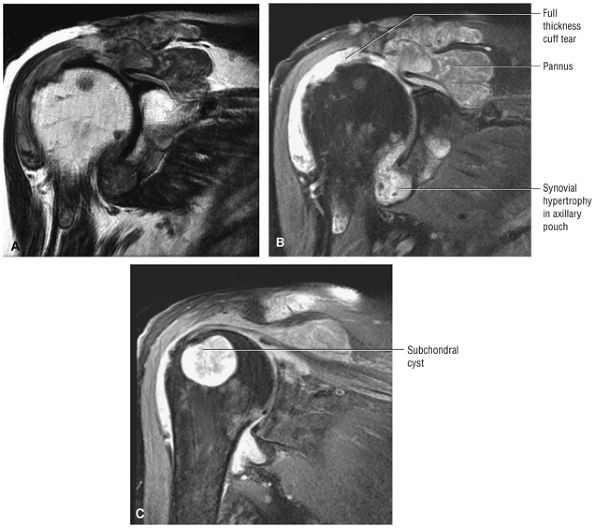

FIGURE 8.102 ● (A) The anterior undersurface of the acromion and the coracoacromial ligament form the coracoacromial arch. The subacromial subdeltoid bursa facilitates the passage of the rotator cuff and proximal humerus under the coracoacromial arch. (B) A superior axial image shows the anterior-to-posterior extent of the coracoacromial (CA) ligament perpendicular to the supraspinatus tendon. The fluid in the subacromial-subdeltoid bursa represents fluid between two serosal surfaces in contact with each other. One serosal surface is contributed by the undersurface of the coracoacromial arch and deltoid, and the other serosal surface is on the bursal side of the cuff.

|

![]() |

FIGURE 8.103 ● Pseudospur. The normal broad attachment of the coracoacromial ligament to the inferior surface of the acromion is shown on (A) T1-weighted coronal oblique and (B) sagittal oblique images. The low-signal-intensity acromial cortex (black arrows) and adjacent coracoacromial ligament and lateral slip of the deltoid attachment (white arrows) give the false impression of a small subacromial spur in the coronal plane. This pseudospur should not be misinterpreted as impingement; otherwise, unnecessary acromioplasties may be performed on patients with a normal coracoacromial ligament attachment and no associated acromial spurs.

-

Impingement syndrome, a clinical diagnosis, is characterized by a range of MR findings from tendinosis to rotator cuff tears.